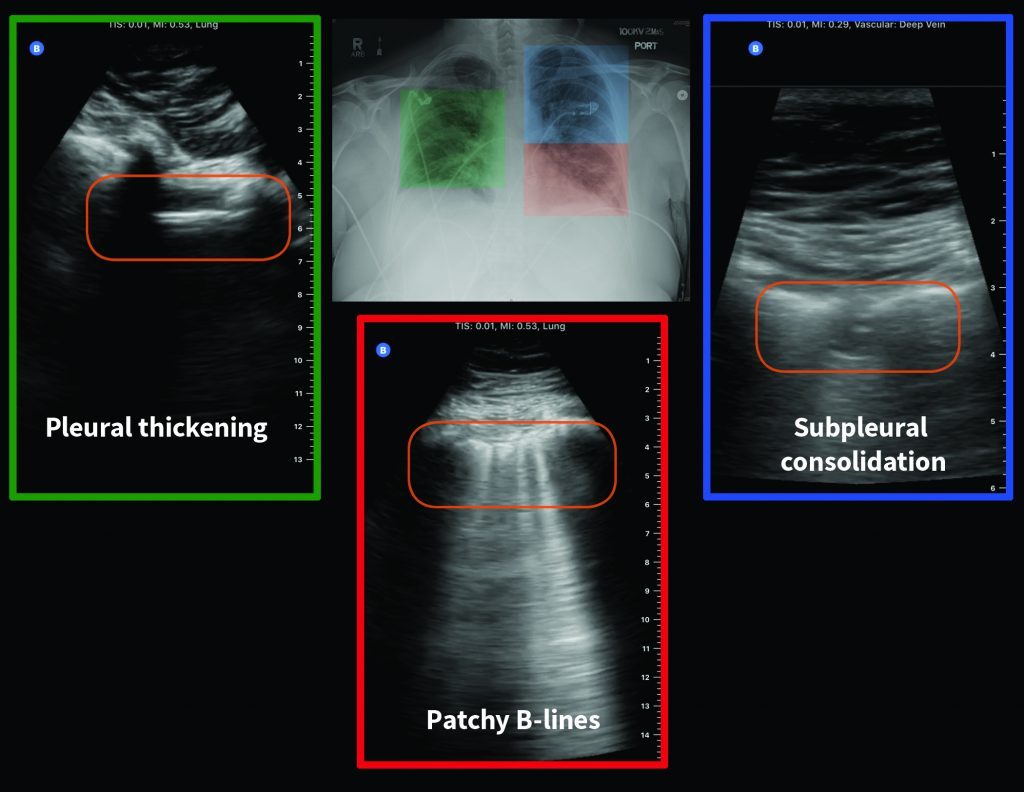

A new study published in the Canadian Medical Association Journal (CMAJ) examined ultrasound images taken from the lungs of a 64-year-old woman diagnosed with COVID-19, revealing how the virus can present itself in the lungs.

Credit: CMAJ. CMAJ

The ultrasound shows “pleural thickening, subpleural consolidation (also known as ‘skip lesion’) and multifocal B-lines,” researchers said.

The pleura are membranes that line the chest cavity and lungs, according to Mesothelioma.net, and they are typically thickened due to scarring, resulting in pleural thickening.

Consolidation occurs when your lungs are filled with something other than air, according to Healthline. It’s common with pneumonia and it often makes it difficult to breathe.

“These images show changes in the lung that occur due to the SARS-CoV-2 virus (which is responsible for COVID-19) infecting the lungs, and the body’s subsequent immune response to the infection,” said Dr. Anish Mitra, a critical care physician in Surrey, B.C.

“These ultrasound images indicate that there is inflammation in the lungs due to the infection.”

According to Mitra, ultrasound images such as these can help to guide treatment in patients with severe cases of COVID-19.

However, ultrasound should not be relied on during the diagnosis stage because inflammation — similar to what is shown in these images — can be seen in other viral pneumonias, including influenza.

“Rather, physicians can use lung ultrasound findings to help them make a diagnosis of COVID-19 or other diseases in the right clinical context,” Mitra said.